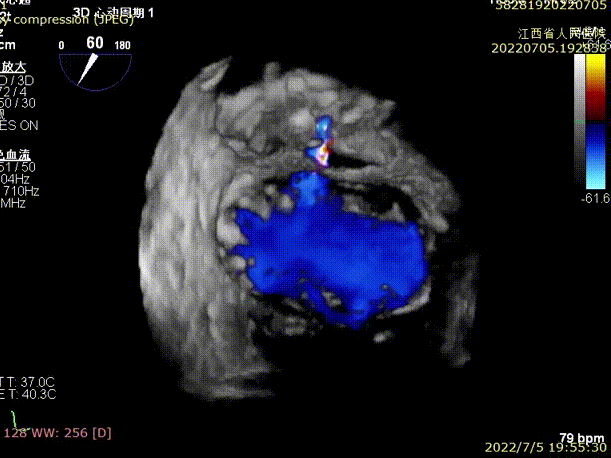

术前TEE显示二尖瓣重度反流,反流位置位于A2/P2区

手术于全麻下进行,采用经典股静脉房间隔途径,房间隔穿刺后置入24F导引导管及二尖瓣夹输送系统,在TEE引导下准确植入一枚二尖瓣夹至A2/P2区,瓣膜夹位置稳定,植入后反流下降至1+,二尖瓣跨瓣平均压力阶差1mmHg,双孔化形成,遂移除器械输送系统。超声心动图评估瓣膜夹位置和功能良好,瓣膜夹活动度低,手术顺利完成。